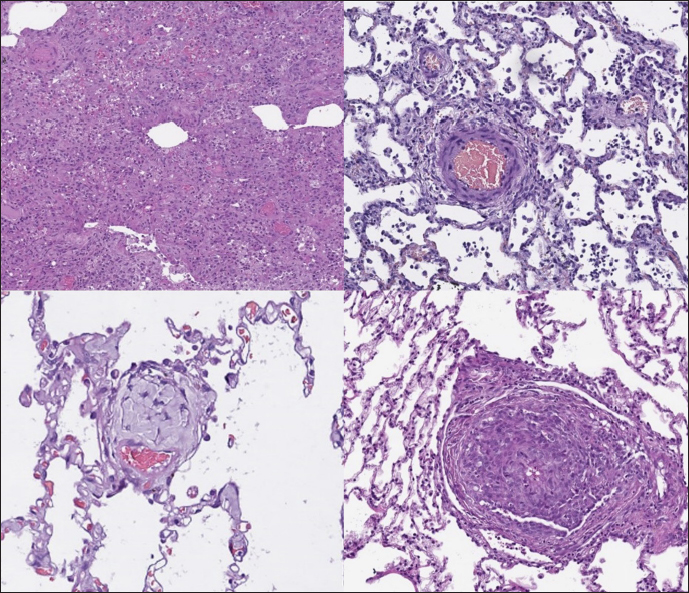

In dogs with RHF, with both Masson’s trichrome and hematoxylin and eosin staining, we found wide fields of pulmonary fibrosis, arterial thickening due to tunica media proliferation, and plexiform vascular lesions with signs of revascularization. The dog with pneumonitis showed chronic interstitial histiocytic pneumonia (Fig. 3).

In the sPCH group, we found zones of multifocal mild-to-moderate alveolar septa thickening with numerous capillary proliferation with signs of congestion. Endothelial cells were flattened, but had no signs of anisocytosis or anisokariosis. The growing capillaries expanded in pulmonary tissue, forming nodules and web-like anastomosis with bizarre vessel proliferation which affects zonal bronchi and arteriolas (Figs. 4 and 5).

Fig. 3. RHF group. Left top—aggressive lung remodeling, resembling organizing diffuse alveolar damage with collapse and fusion of the alveoli and loss of typical structure. Right top—tunica media and adventitia proliferation around pulmonary vessel. Left bottom—partial occlusion of pulmonary vessel. Right bottom—plexiform vasculopathy with lumen obstruction and revascularization, presented with onion-like structure. Stained with H&E.

Fig. 4. sPCH group. Left (dog)—portions of alveolar septae with duplicated capillaries and capillaries proliferation into arterial walls. Right (cat)—less prominent septal alteration, significant arterial walls capillary proliferation. Stained with H&E.

Fig. 5. sPCH group. Net-like capillaries organization in alveolar septa (cat).